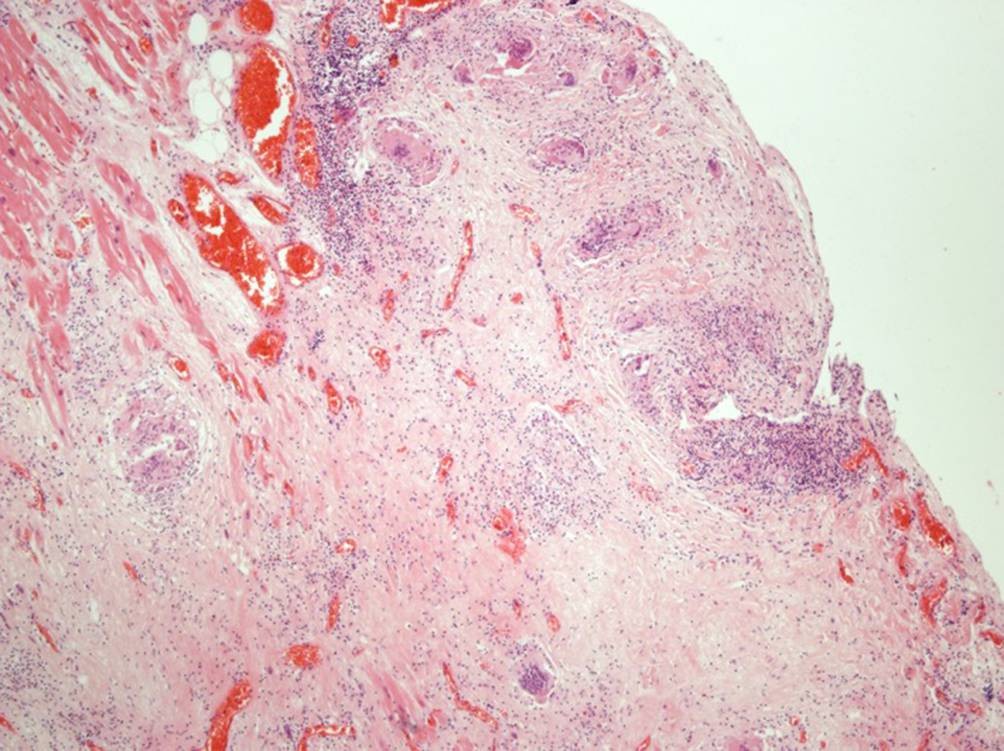

Abb. 2

Ausgedehntes, partiell kapillarisiertes, fibrosiertes Areal im Myokard mit unspezifischer chronischer lymphozytärer Entzündung und fokal anzutreffenden mehrkernigen Riesenzellen (HE, Vergr. 40:1)